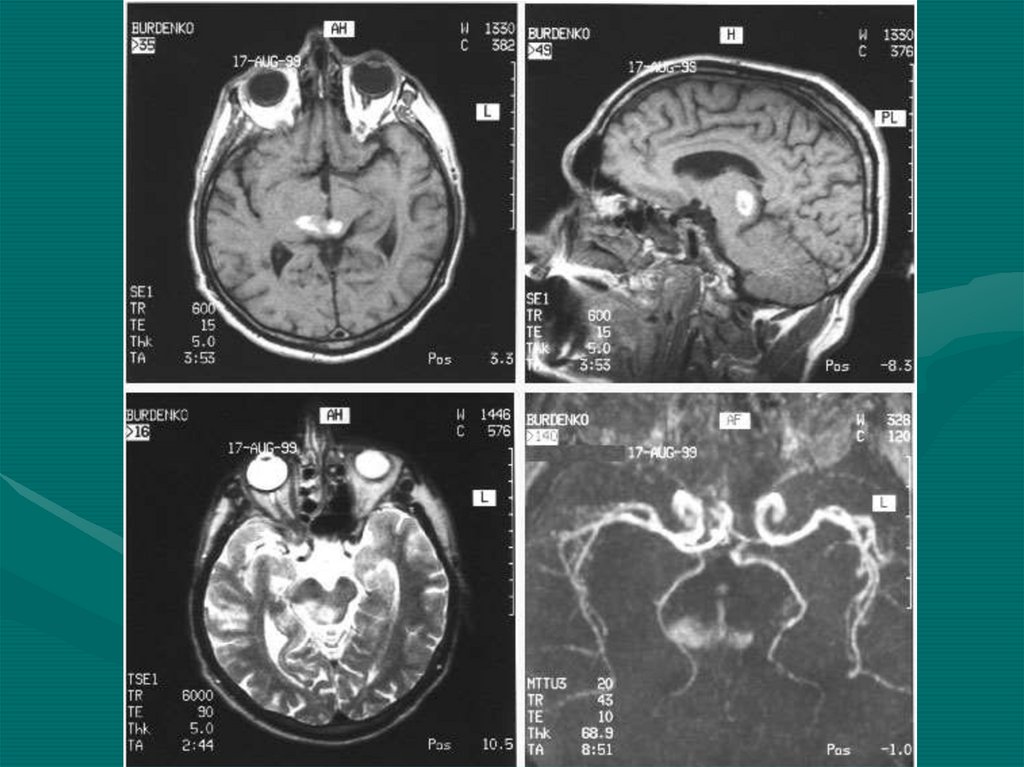

12. ЯМР-резонансная группа

• МРТ (Магнитно-резонансная томография)

• МРС (Магнитно-резонансная спектроскопия)

• Позитронно-эмиссионная томография

• Энцефалосцинтиграфия

• Энцефалоангиосцинтиграфия